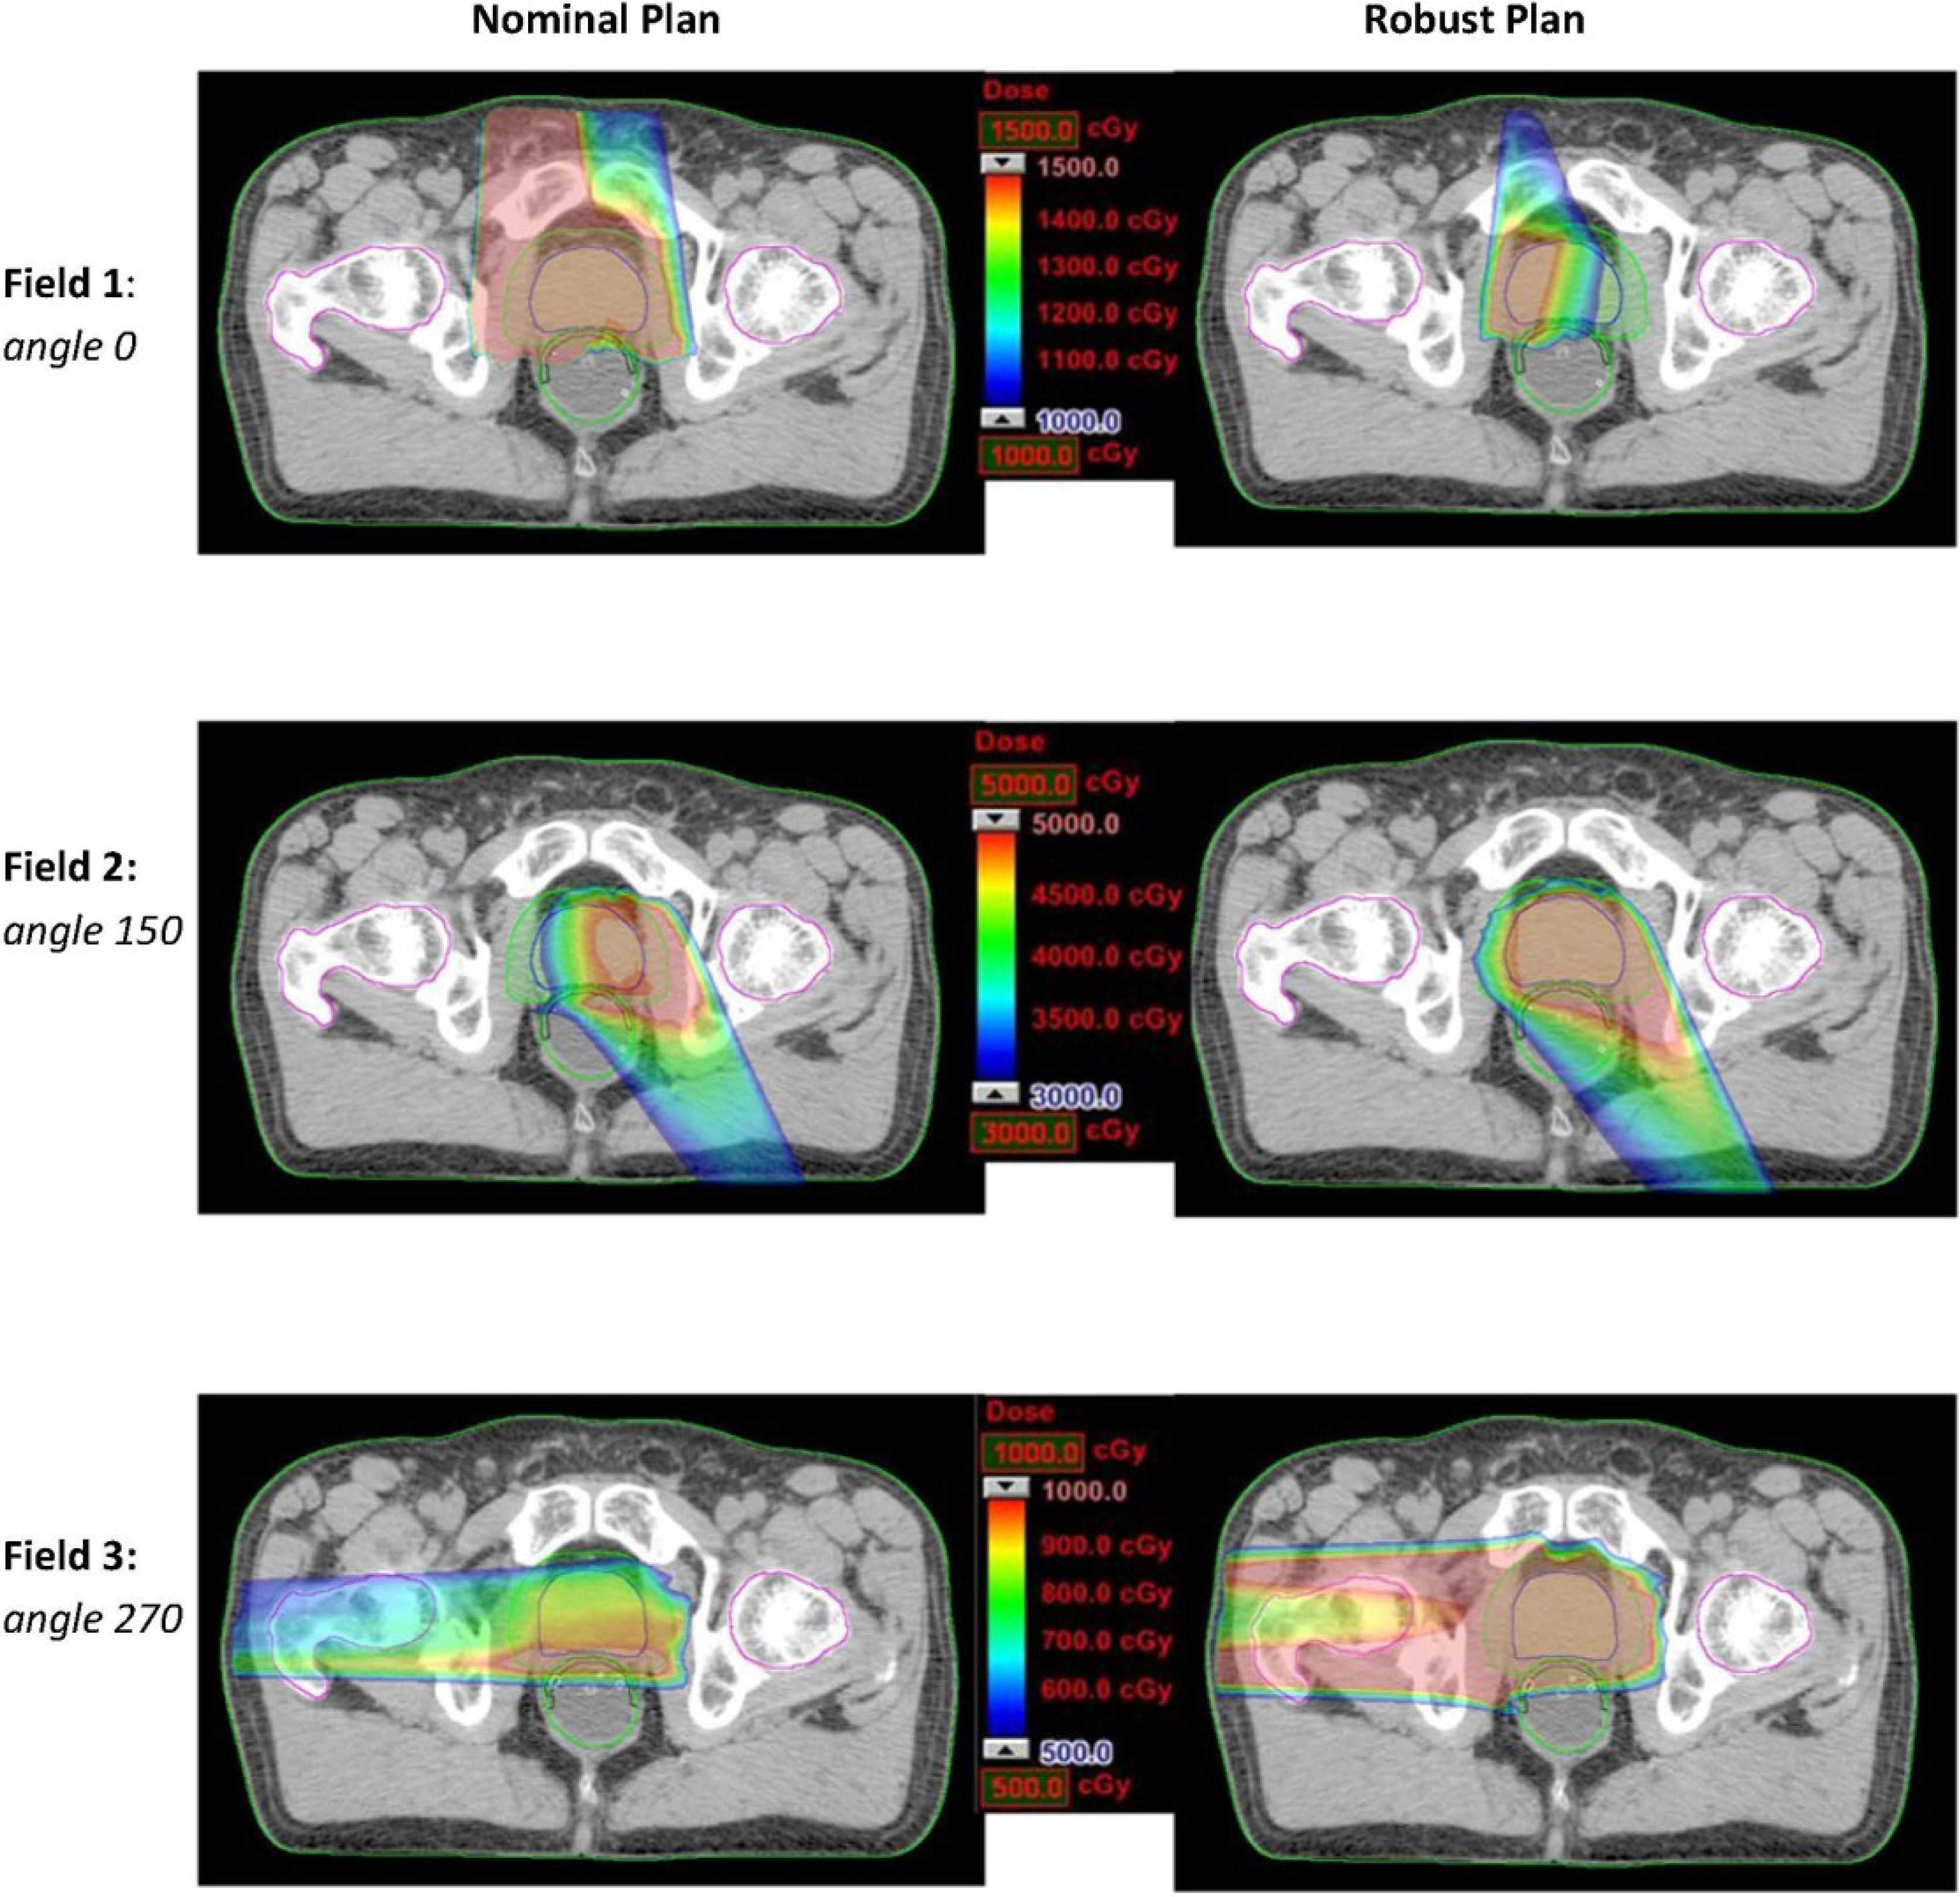

Under the worst-case scenario, the significant reduction of dose on rectum by three-beam plans comparing to two-beam plans was consistently preserved. This indicates the three-angle plans are still preferable upon the realization of certain uncertainties. In addition, one can also apply robust optimization for mitigating uncertainty effects. Due to the high flexibility of IMPT, intensity modulation of proton beams can enable incident fields to produce individually inhomogeneous dose distributions while their combination forming a homogeneous and robust dose distribution. Figure 3 shows an example of a robustly optimized three-beam plan (patient 2) using a robust optimization algorithm [25] in comparison with a nominally optimized plan. The robust plan tends to limit dose coverage by the beam incident from the zero-degree gantry angle, while providing more uniform dose coverage by angles 150° and 270°. In contrast, the nominal plan includes more uniform dose coverage by angle 0°. Ultimately, the sensitivity to uncertainties can be mitigated from the nominally optimized to the robustly optimized plan for the same set of treatment beam angles. Figure 4 shows the dose volume histograms for the clinical target volume (CTV) and the rectum from nominal and worst-case dose distributions based on nominally and robustly optimized plans for the same patient (shown in Figure 3).

Figure 3.

Dose distributions (per field) in the transverse plan for comparing the nominally optimized and robustly optimized three-beam IMPT plan for one prostate cancer patient.